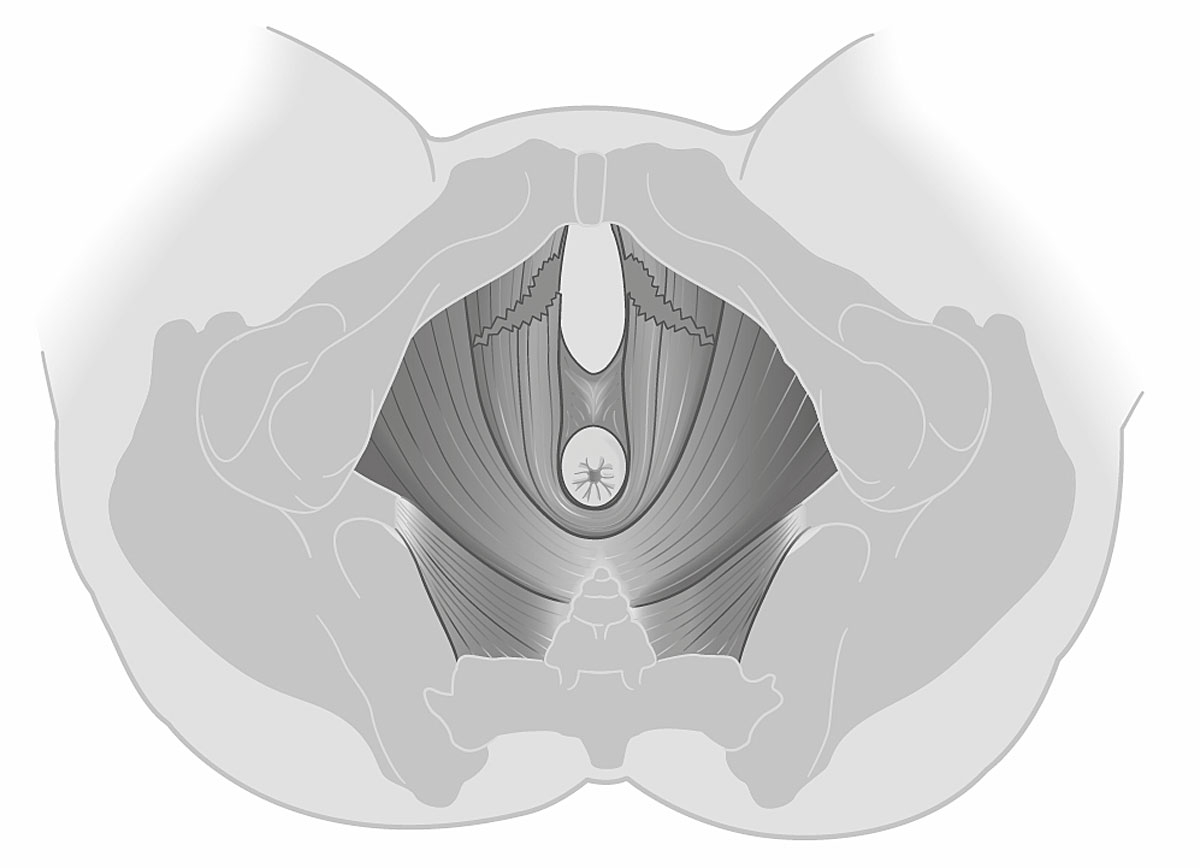

Of the 49 women with vacuum-assisted births in our cohort, 32 (65.3%) had an intact levator ani muscle, as shown in the illustration in fig. 2a and in the 3D ultrasound scan in fig. 2b. In contrast, 17 (34.7%) sustained levator ani muscle trauma, with 9 women (18.4%) having a partial levator ani muscle avulsion and 8 women (16.3%) having a complete levator ani muscle avulsion, as shown in the illustration in fig. 3a and in the 3D ultrasound scan in fig. 3b. No significant differences between the two groups were found, except for the state of their uterine contractions. Women without any levator ani muscle injury after vacuum extraction had more efficient uterine contractions compared to women with levator ani muscle trauma.

Figure 3a Illustration of a complete bilateral levator ani muscle avulsion.